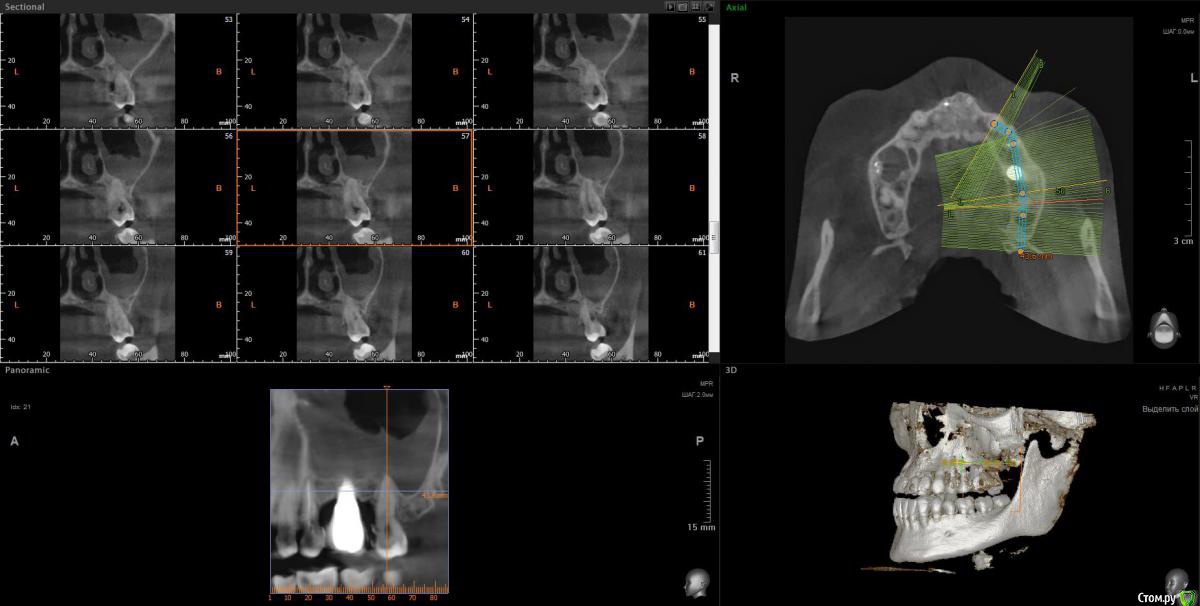

wladdX Опубликовано 9 апреля, 2020 Поделиться Опубликовано 9 апреля, 2020 Несколько скринов Ссылка на комментарий

Lunar Опубликовано 9 апреля, 2020 Автор Поделиться Опубликовано 9 апреля, 2020 Несколько скринов25_1.jpg25_2.jpgimp_1.jpgimp_2.jpg27_1.jpg27_2.jpgспасибо за скрины Ссылка на комментарий

Irouil Опубликовано 9 апреля, 2020 Поделиться Опубликовано 9 апреля, 2020 https://yadi.sk/d/FRKX9i80axqaUgПосмотрел я Ваше КТ. На мой взгляд, проблема чисто ЛОРовская, но... ЛОР врач может придраться к состоянию в полости рта и формально будет прав, поэтому Сначала проверить на витальность 7ку (вероятнее всего все же придётся депульпировать) Клинически осмотреть 5-ку (стоматологу терапевту). Потом к лору. Имплантат к пазухе вообще не имеет никакого отношения 1 Ссылка на комментарий

Irouil Опубликовано 10 апреля, 2020 Поделиться Опубликовано 10 апреля, 2020 Ну, вообще определённые вопросы к имплантату и по КТ, и по фото во рту есть. Но не связанные с пазухой Ссылка на комментарий

Irouil Опубликовано 10 апреля, 2020 Поделиться Опубликовано 10 апреля, 2020 На мой взгляд удалять имплантат пока не надо, но нужна очная консультация пародонтолога и новая коронка на имплантате Ссылка на комментарий